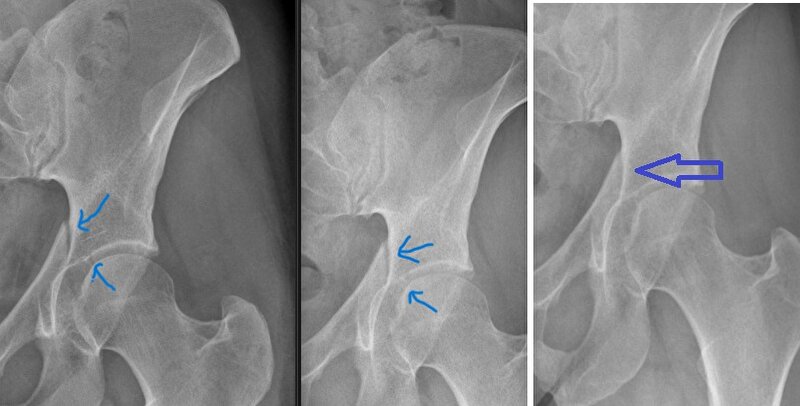

Earth schreef:Ik heb alleen nog steeds een kneuzing in mn heup zitten waar ik met slapen wat last van heb. Iemand een idee wat ik daarmee kan doen? Of is dat ook een kwestie van bewegen?